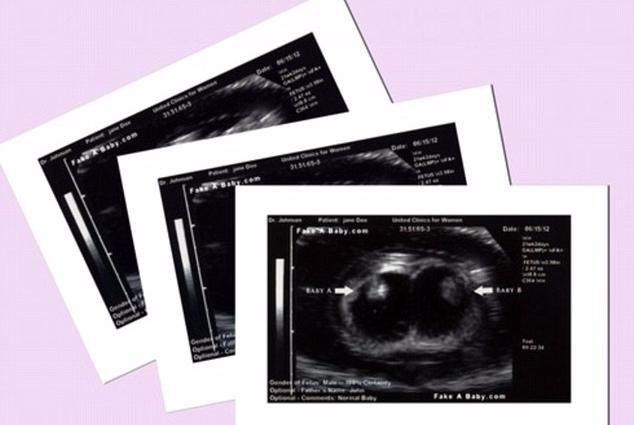

Cùng lúc ấy, một thành viên của nhóm “Moms of Triplets” phát hiện điều bất thường trong hình ảnh siêu âm cô gái đã đăng trên mạng nên đã liên lạc với gia đình. Hóa ra tất cả những ảnh siêu âm đều là giả, ngay cả cái bụng bầu cũng là đồ giả và được cô gái tìm mua trên trang mạng chuyên bán các loại phụ kiện giả bụng bầu.

“Hình siêu âm của 3 đứa bé giống hệt hình chúng tôi thấy trên mạng”, Tracy Matthews, một người bà con của Jordan lên tiếng.

Hình ảnh siêu âm giả.

Trang web bán đủ mọi phụ kiện để giả mang thai, từ bụng bầu đến hình siêu âm.